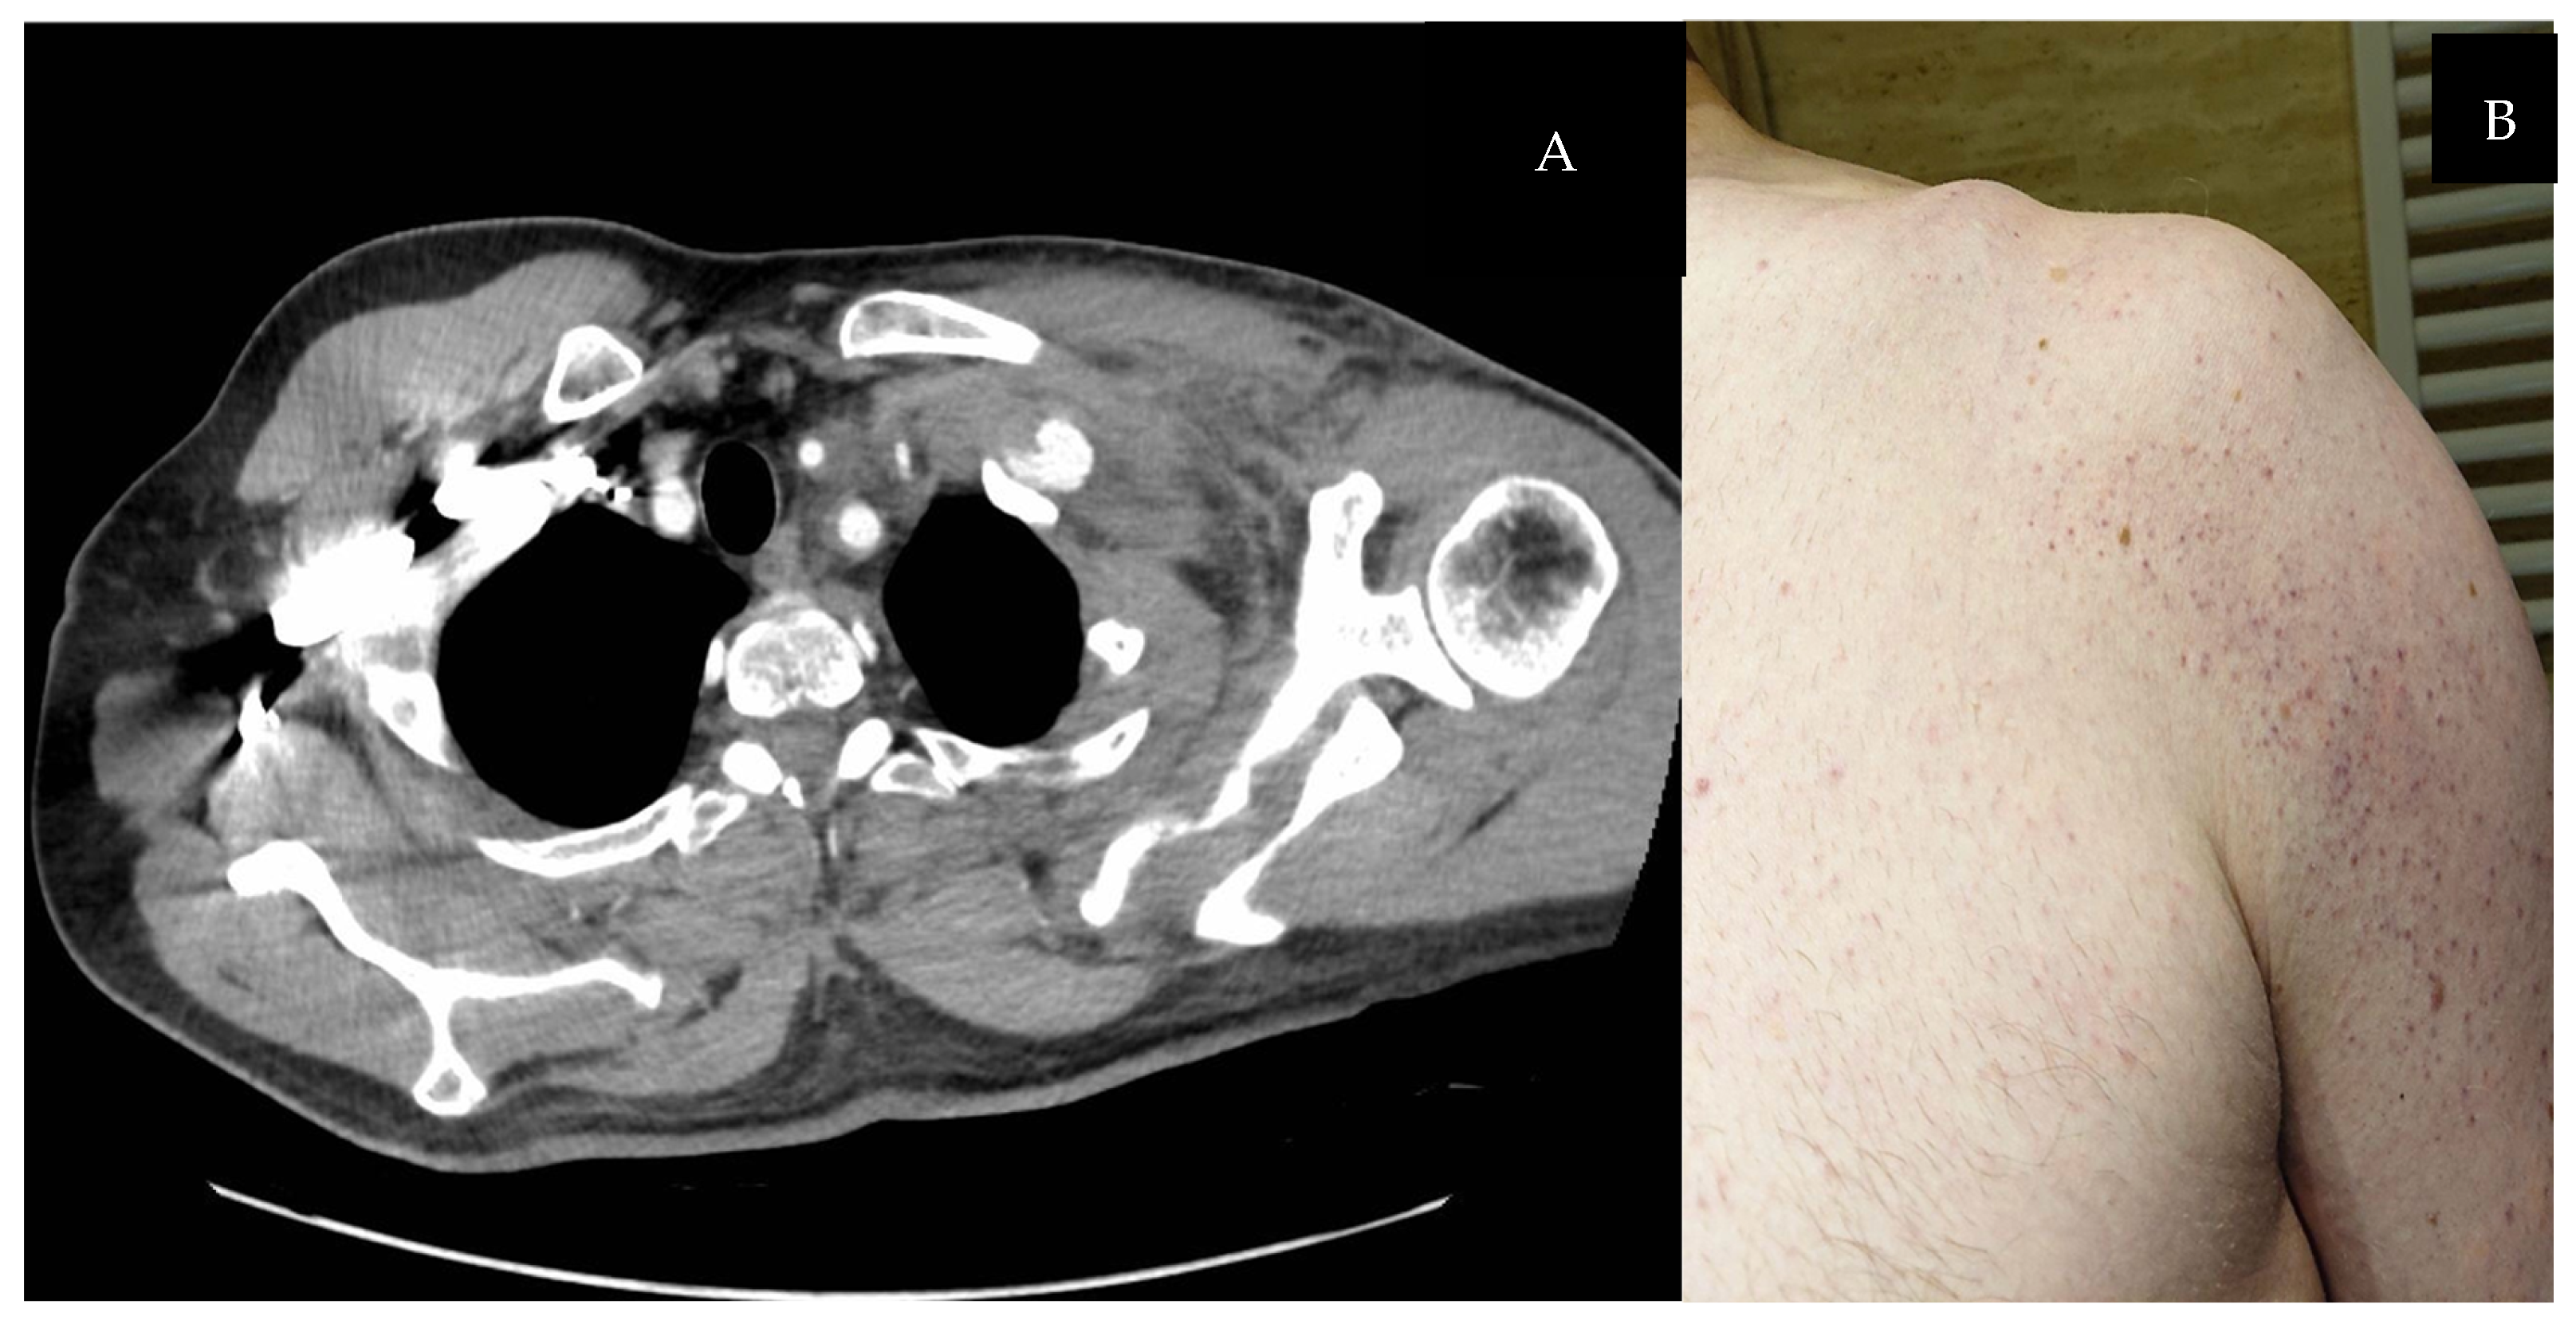

| 20 | Presented case | M | 49 | Fracture of the clavicle and ribs II to VII on the left side, left SCVT, hypertension. | 4 | Swelling in the left supraclavicular area, left-sided chest pain, subclavicular and brachial vein thrombosis | Upper limbs symmetrical, without swelling, with palpable pulse on the radial arteries | Left | NR |